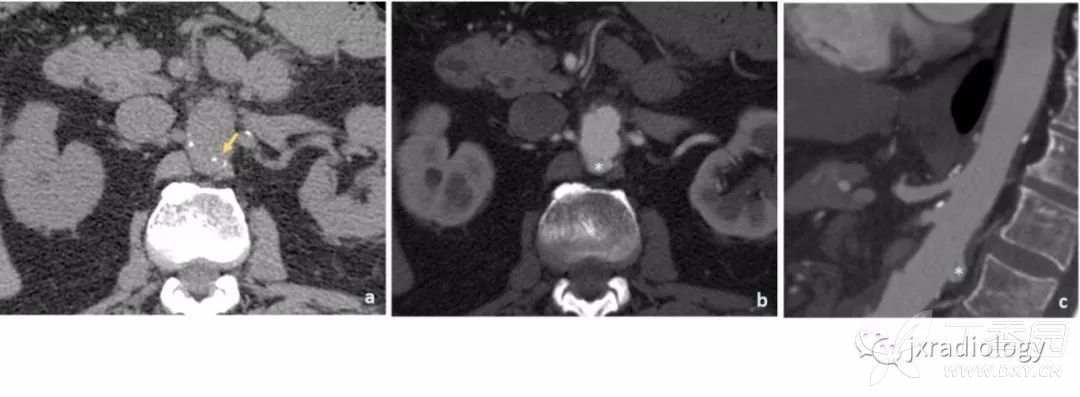

图9:增强CT显示罕见的多腔型主动脉夹层的病例。

可见两个假腔,内膜瓣延伸至腹腔干(a图箭头所指)和肠系膜上动脉(b图箭头所指)。